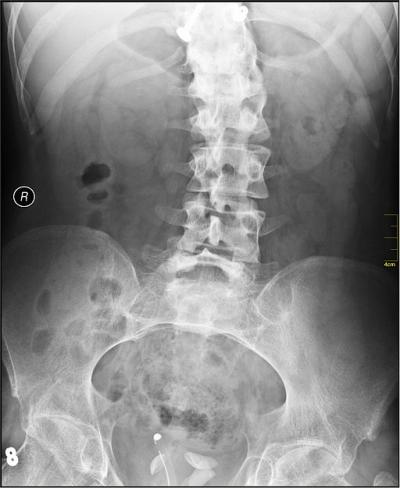

Adolescent idiopathic scoliosis--a condition featuring curvature of the spine--affects tens of millions of children worldwide, but does not have a known cause. Now, scientists at the RIKEN Center for Integrative Medical Sciences in collaboration with Keio University in Japan have discovered a gene that is linked to susceptibility to the condition. Published in the American Journal of Human Genetics , the work details how the susceptibility gene is associated with increased expression of the protein BNC2, which is in turn regulated by another protein called YY1.